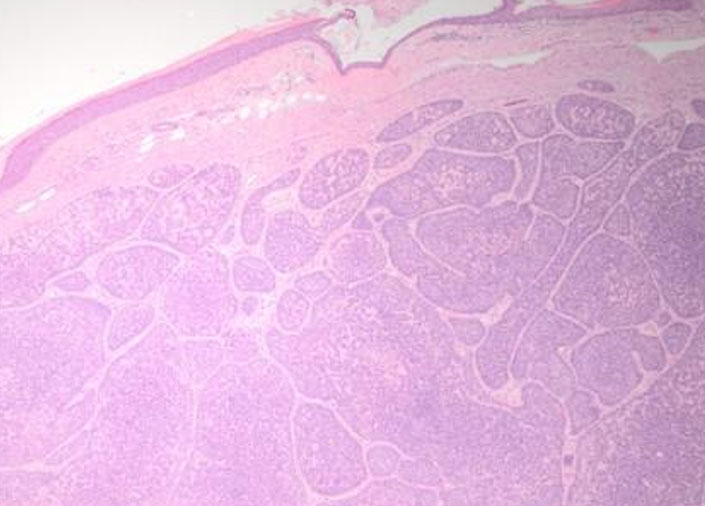

Microscopic examination showed a poorly circumscribed, unencapsulated dermal based tumor composed of multiple variably sized, irregularly shaped basaloid nests and islands of basaloid cells, separated and ensheathed by an eosinophilic hyalinized band like basement membrane, forming the characteristic “Jigsaw puzzle” like pattern of a cylindroma (Figure 1 and Figure 2). A band of compressed papillary dermis was appreciated separating the dermal based basaloid islands from the overlying epidermis, without any appreciable connection. The islands were composed of smaller, bland appearing basaloid cells with hyperchromatic nuclei mostly located at the periphery of the islands, with larger paler cells with vesicular shaped nuclei within the central areas. Focal duct like formations were seen, along with globules of brightly eosinophilic hyaline basement material within the islands. Near the periphery of the tumor, mature adipocytes were seen separating the dermal basaloid nests with surrounding eosinophilic bands, expanding the stroma between nests, distributed circumferentially up towards the papillary dermis (Figure 3 and Figure 4). No necrosis, nuclear atypia, or mitotic figures were identified.

Figure 2: Higher power view of poorly circumscribed nests ensheathed by eosinophilic bands, forming a complex “jigsaw puzzle” like pattern. The nests contain small globules of hyaline basement material. Dual population of smaller hyperchromatic cells at the periphery and larger, paler vesicular cells centrally also can be seen (H&E, 100×).

Figure 3: Periphery of tumor showing dermal basaloid nests with surrounding eosinophilic bands, with mature adipocytes present and expanding in the stroma between nests (H&E, 200×).